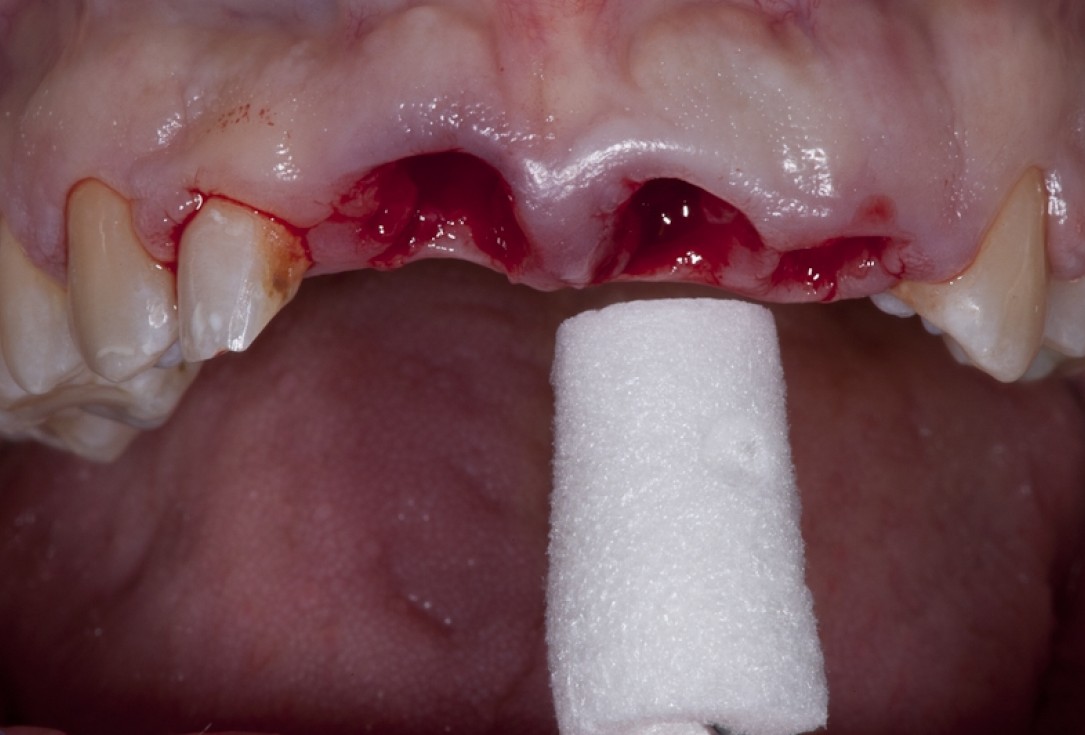

Socket preservation with permamem® - Dr. R. Rannula

Situation after tooth extraction.